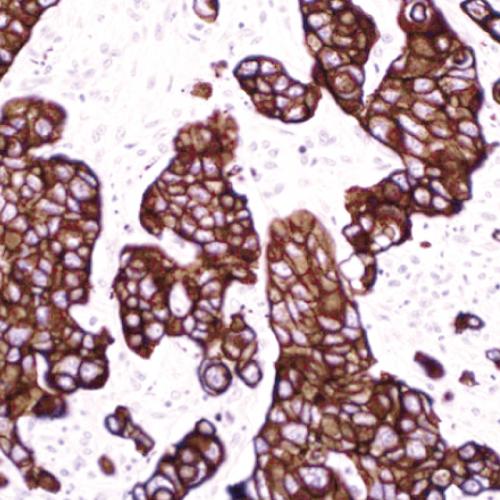

由于組織中富含免疫球蛋白,因此采用免疫組化技術(shù)檢測Lambda會伴隨大量背景染色的形成,這將影響染色結(jié)果判讀。而原位雜交探針具有高度特異性,在石蠟切片中容易涉透到組織中去與靶標(biāo)雜交,并且得到穩(wěn)定優(yōu)質(zhì)的染色結(jié)果。

Lambda鏈探針試劑,分別針對Lambda鏈mRNA序列特異設(shè)計靶點檢測,具有高度特異性和敏感性。通過多聚體酶標(biāo)技術(shù)-DAB顯色系統(tǒng),極大提高了檢測信號強(qiáng)度。